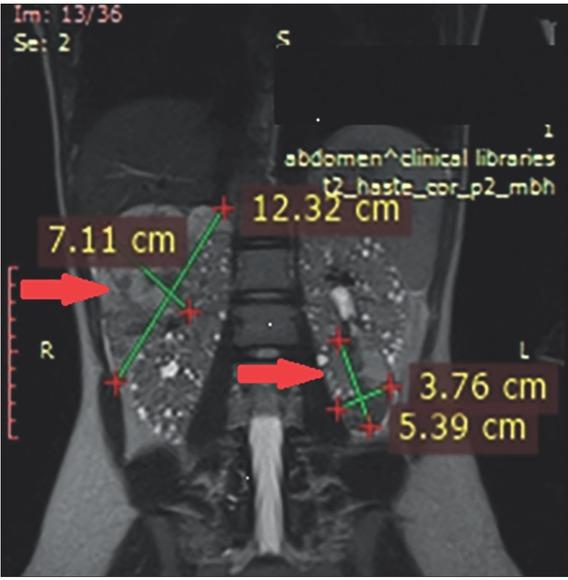

Magnetic resonance imaging of the urinary tract and brain were performed before initiation of everolimus treatment (Figures 1 and 2). After 12 months of treatment, reduction of the renal tumors and SEGA were registered (Figures 3 and 4). At 36 months, ~24.0% reduction in the longest diameter of the largest AML in right kidney was achieved. Reduction of SEGA was also observed (Figures 5 and 6). All biochemical parameters remained stable during the follow-up period. Normal renal function without a new onset of proteinuria was observed (Table 2).

Figure 1

At the upper pole of the right kidney a large AML, longest diameter of 12.3 × 7.1 cm (arrow left) with heterogenous density, presence of microaneurisms at the posterior and lateral segments, with a dominant lipid component revealed on the urinary tract MRI (red arrow). At the lower pole of the left kidney, an AML with the dimension of 5.3 × 3.7 cm (arrow right) and other multiple AMLs with dimensions of 5-10 mm were found, as well as multiple cysts.